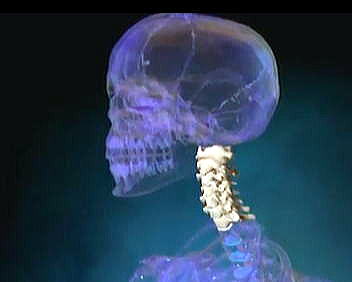

午前8時半に到着するが、私が実際に診察、検査を受けたのは午前10時過ぎからである。当直の若い医師(慈恵医大病院から当直でこの曜日のこの時間だけ勤務されていた入江医師)が私にCT撮影を指示。CTデータをもとに診断した。 最初、「問題はなさそうです」と言われたが、その直後、再度CT画像を検証したところ、ひょっとすると第二頸骨が折れている可能性があると指摘した。骨折を精査するためにMRI検査を私に指示、MRIデータをもとに診断し骨折を最終確認した。 CT画像は、断層となっているため断面(側面、立面)によって見え方が著しく異なる。確かにある角度から見ると骨折が見えにくいが、他の角度から見るとはっきりと骨折が確認できた。入江医師は、私と妻にCT及びMRIのパソコン画面を見せながら、慈恵医大付属病院への推薦状を書かれ、2~4週間の入院と手術が必要との見解を述べた。旗の台脳神経外科で簡易ギブスを提供し着用を指示した。 ◆慈恵医大付属病院の脳神経外科で本格検査 上述のように旗の台脳神経外科の医師は、翌朝一番、11月11日(実は青山の誕生日)午前8:00時に慈恵医科大学病院の外来に行くよう指示をくれた。 翌日、11月11日(青山の誕生日)、妻の運転で朝一番に慈恵医大病院地下一階の脳神経外科に外来患者としてゆく。 脳神経外科の大橋医師は、入江医師からの推薦状を読み、かつ旗の台脳神経外科から持参したCT,MRIデータを元に、第二頸椎骨折を確認する。 大橋医師はまず最初に、慈恵医大付属病院の1階奥に国際標準のギブス(英語ではカラーという)を提供する部署があり、すぐに提供してくれた。費用は保険適用前は約2万5千円、保険適用で3割負担となるが、ここではとりあえず全額を支払う。 下に私が付けているカラーの実物の写真を示す。大きさは何種類かあるが、私の場合は小(Small)である。顔などに当たる部分はすべてスポンジが入っている。スポンジのスペアーが付属し、定期的に洗濯したものと付け替える。  首に装着する簡易ギブス(=カラー) 検査時に装着を義務づけられたカラーは、その後、手術時以外、現在に至るまで常用を義務づけられた。もちろん、就寝時も。 あとで知ったのだが、実は上述の入江医師と大橋医師は、日本を代表する若手の脳神経外科であった。これが幸いした。早期段階で頸椎の骨折、陥没を的確に診察し、手術の必要性を判断したことで一命を取りとめることができたと言ってもよいだろう。先送りするのではなく、すぐに手術することを命じてくれたのである。 2人の脳神経外科の専門医師は、ともに私と同席した妻に繰り返し「九死に一生、青山さんは非常に運が良かった」と言ってくれた。最初はぴーんと来なかったが、説明を受け自分で調べるに及んでその意味が分かってきた。  東京都港区にある慈恵医大病院 出典:慈恵医大病院公式Web

下はいわゆるレントゲン撮影装置。下の装置は任意の部位を撮影可能。口を大きく開けた奥が第二頸椎なので口から照射し頸椎を撮影したり、術後の状況を詳細に撮影したりした。実際、口を大きく開けて頸椎をレントゲン撮影した。フィルムを技師から見せてもらったが、まさにのど仏が写っていた。くわばらくわばらである!  任意の部位が撮影可能なレントゲン撮影装置(イメージ図) 口を大きく開けるといわゆるのど仏が見える。これが第二頸椎である。初動検査の11月11日、上記のレントゲン撮影器を使い、大きく口を開けることで何と、口側から頸椎を撮影した。ただし、下の写真はイメージ図であり私の頸椎を撮影したものではない。  出典:http://www.orihime.ne.jp/~one-/tekious.htm ◆第二頸椎骨折のCT、MRI画像 後日、慈恵医科大付属病院からCT及びMRI断層画像の提供を受けた。 下はCT断層画像に見る第二頸骨の骨折(2010年11月11日撮影)である。頸椎が斜めに骨折しているのが分かる。もっぱら、CTであれMRIであれ、実際に折れている箇所を探すのは容易ではない。専門医ですら同じだ。  CT断層画像に見る青山貞一の第二頸骨骨折(2010年11月11日撮影)。 出典:慈恵医大付属病院脳神経外科  MRI画像に見る青山貞一の第二頸骨骨折(2010年11月17日撮影)。 第二頸椎が断層的に骨折していることが分かる!! 出典:慈恵医大付属病院脳神経外科 つづく |